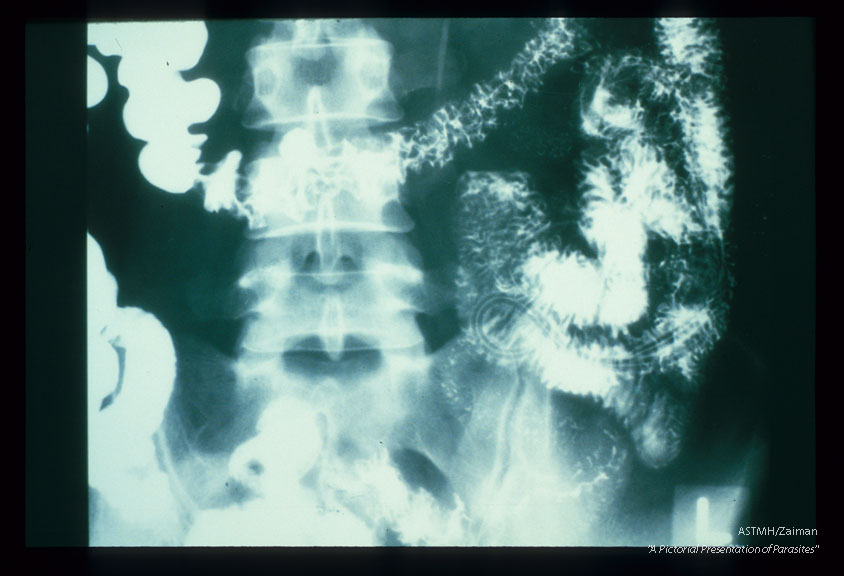

Small bowel barium study shows adult worms which present as longitudinal dark lucencies against the white barium in the small bowel. The worms have ingested the barium. Their guts present as white longitudinal line bisecting the dark lucencies which represent the worm bodies.

Ascaris lumbricoides

Description: Small bowel barium study shows adult worms which present as longitudinal dark lucencies against the white barium in the small bowel. The worms have ingested the barium. Their guts present as white longitudinal line bisecting the dark lucencies which represent the worm bodies.